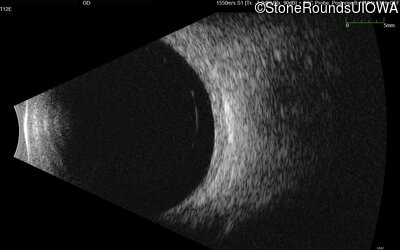

B-Scan Ultrasonography - Right - Light Perception

Exemplar

B-Scan Ultrasonography - Left - Light Perception